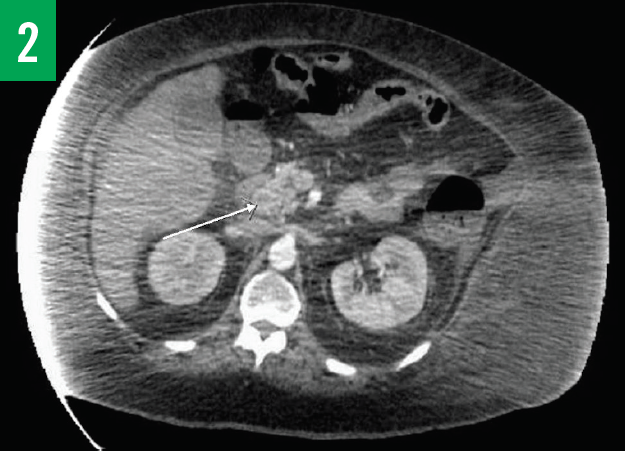

Computed tomography (CT) scans of the chest and abdomen/pelvis showed innumerable low-attenuation lesions scattered throughout the liver, with the largest measuring up to 5.5 cm in diameter (Figures 1A-1C); the lesions were likely related to metastasis. A questionable lesion was also noticed at the head of the pancreas (Figure 2), and the scan showed bowel-wall thickening involving the proximal descending colon (Figure 3).

Figure 2. CT scan with contrast of the chest showing a questionable lesion at the head of pancreas.